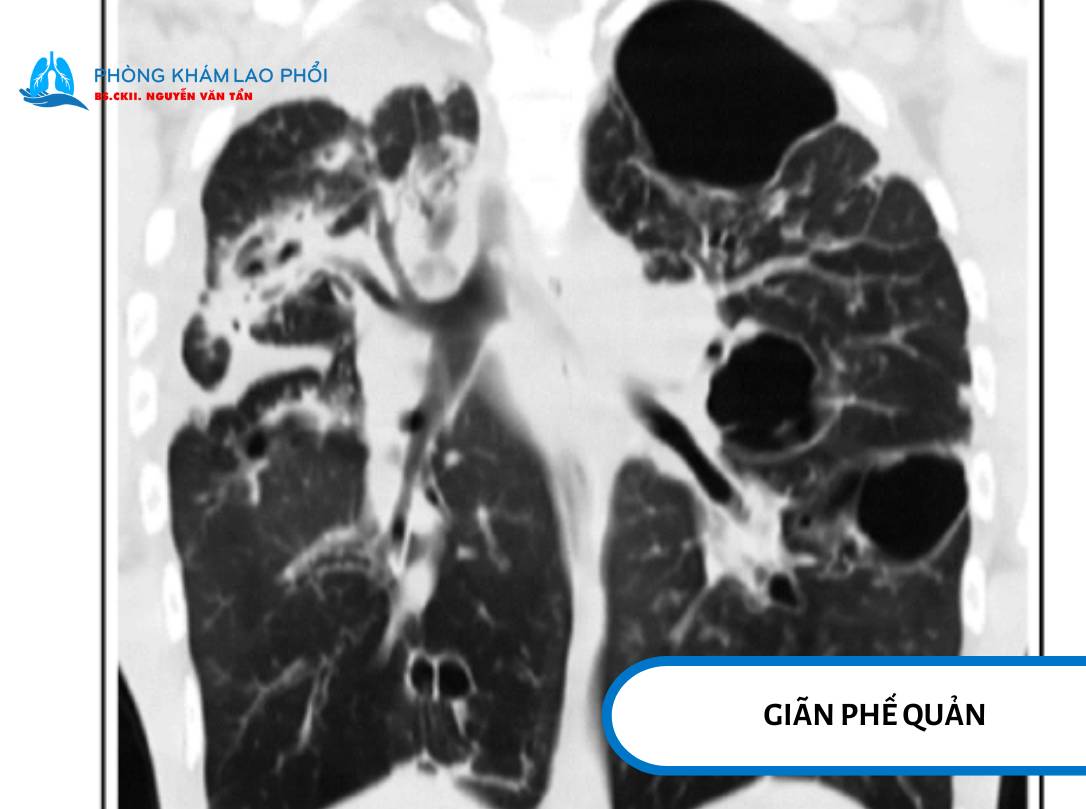

Giãn phế quản

Giãn phế quản là khi phế quản mất cấu trúc đàn hồi do dây xơ, viêm mạn, phá hủy thành ống khí.

Triệu chứng: ho kéo dài, khạc đờm nhiều, dễ nhiễm trùng tái phát, có thể có mủ trong đờm.

Nguy cơ ho ra máu, đặc biệt nếu có viêm niêm mạc hoặc tổn thương mạch máu trong ống phế quản.